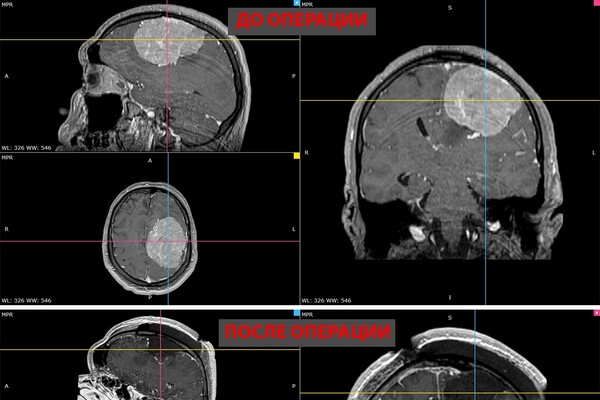

В Новосибирске врачи удалили 35-летнему пациенту гигантскую опухоль головного мозга. Об этом сообщает пресс-служба НМИЦ имени Мешалкина Минздрава России.

В ноябре прошлого года у мужчины появилась слабость в правой руке и затруднения речи — МРТ выявила у него менингиому диаметром более восьми сантиметров в левом полушарии мозга. К концу года рука практически перестала работать, ходьба давалась пациенту с трудом.

Пятичасовая операция прошла успешно. Опухоль удалили полностью. Уже на следующий день появились движения в руке, через две недели пациент снова стал сам ходить. У него восстановились речь и движения, приступы исчезли.